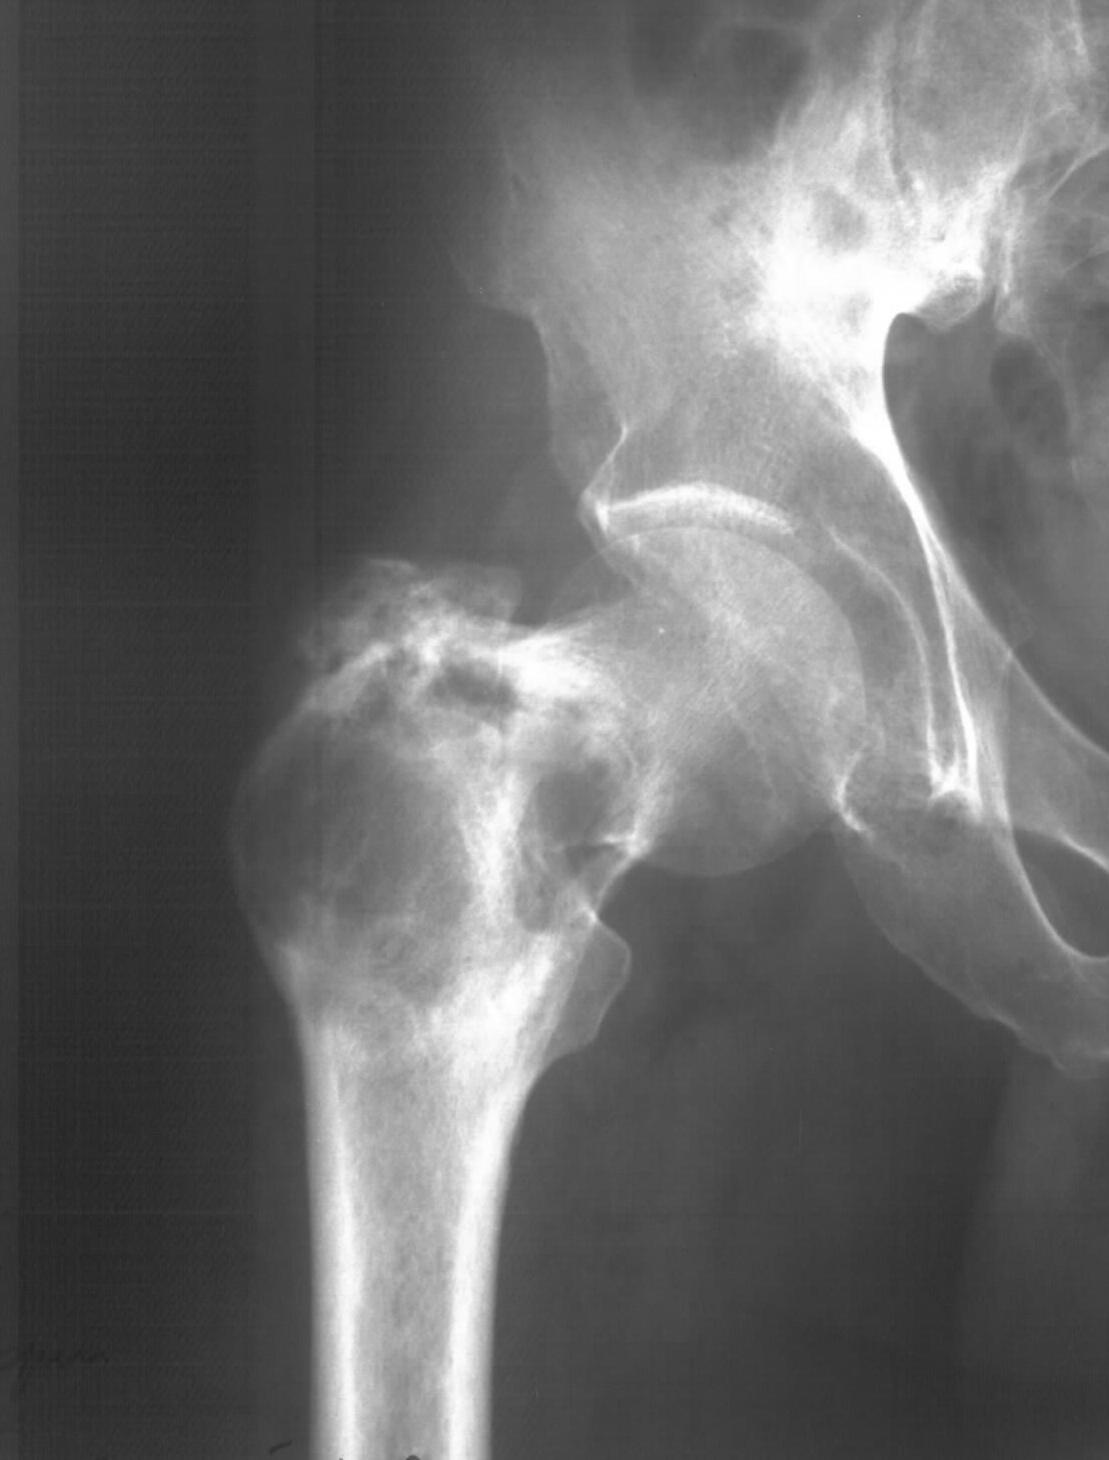

Диагноз: Ангиосаркома проксимального отдела правой бедренной кости. Патологический перелом шейки бедренной кости. Множественные метастазы в легкие, позвоночник, ребра, кости таза.

Считает себя больным с 2005 года, когда впервые появились боли в правом тазобедренном суставе с иррадиацией в поясничную область. Лечился по месту жительства по поводу поясничного остеохондроза, люмбоишиалгии. Отмечает постепенное усиление болей в области правого тазобедренного сустава. С августа 2007 года появилась хромота. В 2008 году была выполнена рентгенография тазобедренного сустава, выявлен патологический очаг в проксимальном отделе бедренной кости. Консультирован онкологом. Обследовался стационарно в травматолого-ортопедическом отделении №1 ГУЗ «СККЦ СВМП». Была выполнена операционная биопсия. Заключение: «наиболее вероятна картина гемангиоэндотелиомы с явлениями пролиферации и атипии». Для дальнейшего лечения был направлен в РОНЦ им. Н.Н.Блохина РАМН. Повторно была выполнена операционная биопсия с иммуногистохимическим исследованием материала. Заключение: «морфологическая картина более всего соответствует ангиосаркоме». Получил курс лучевой терапии. Планировалась повторная госпитализация для органосохраняющего оперативного лечения. Однако до настоящего времени госпитализация не состоялась.

31.05.09 упал дома с высоты собственного роста. Появились сильные боли в правом тазобедренном суставе. Самостоятельно обратился в ГУЗ «СККЦ СВМП». При клиническом обследовании и рентгенографии был диагностирован патологический перелом шейки бедренной кости.Объективно:

Судя по КТ опухоль кроме шейки захватила большой трохантер и частично головку бедра. На мой взгляд, даже самое удачное расположенние винтов гвоздя не позволит больному полностью наступать на ногу. Протез же позволит больному максимально улучшить качество оставшейся жизни с раннего послеоперационного периода.